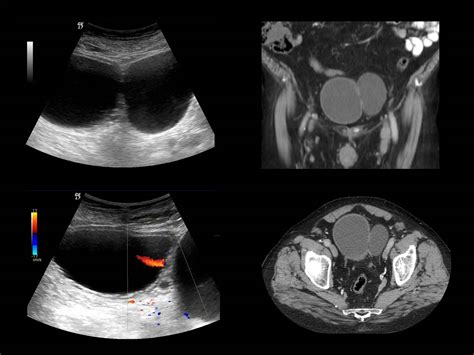

Diagnosing a Urinary Bladder Diverticulum requires imaging to visualize the bladder structure. Urologists typically utilize a combination of the following methods:

Ultrasound Non-invasive method to visualize the presence and size of the diverticulum.

CT Urography Provides detailed images to rule out stones or tumors within the pouch.